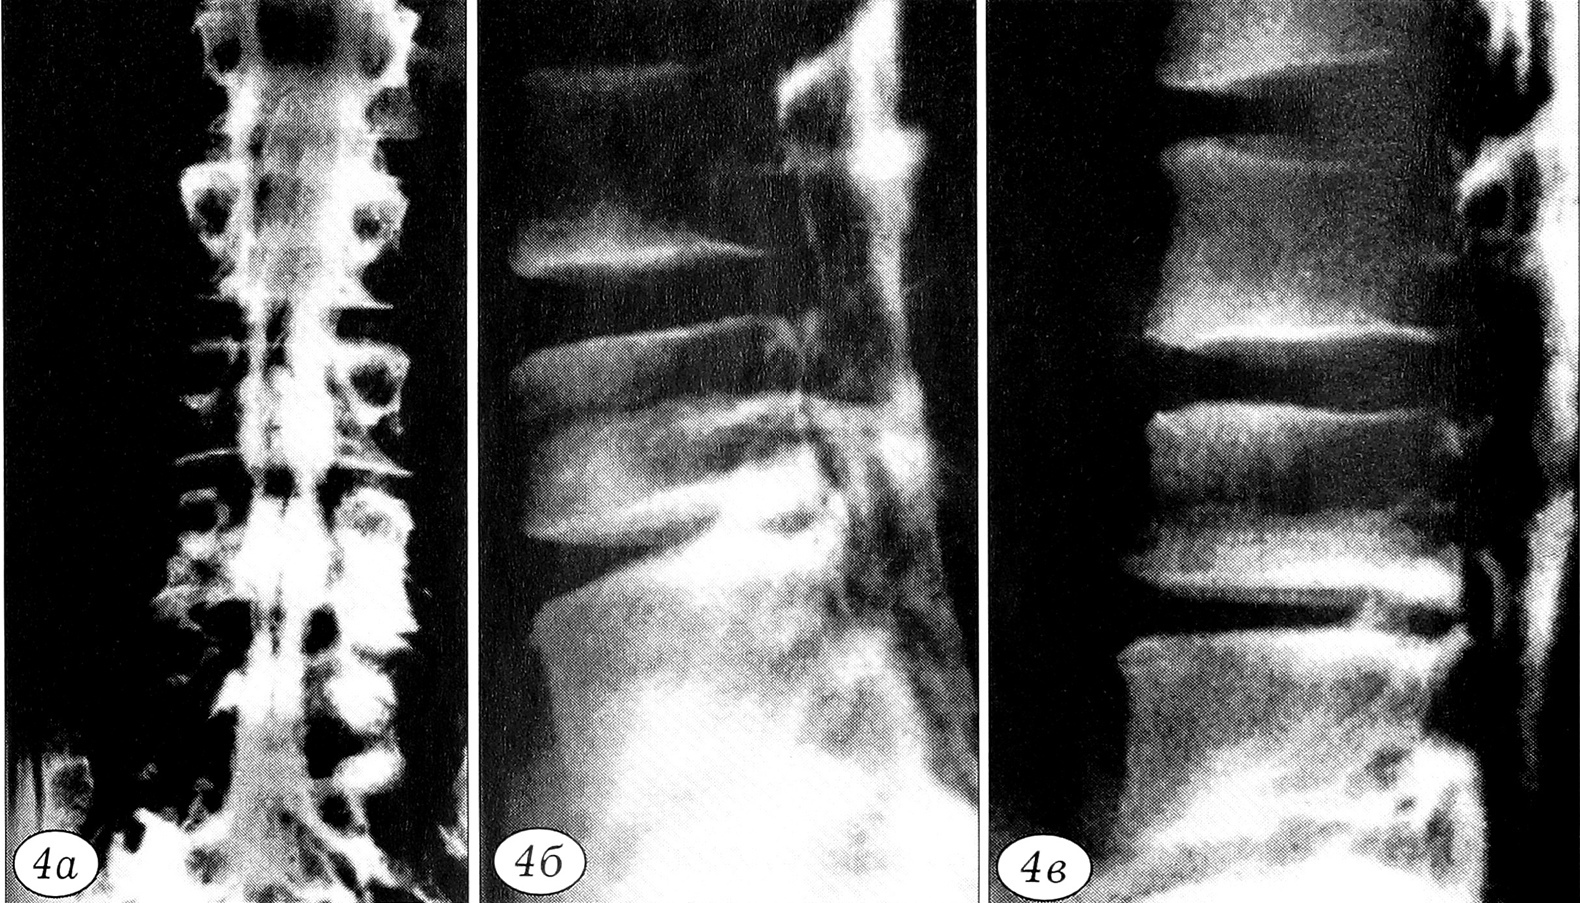

Рис. 4. Эпидурограммы (а — прямая, б, в — боковые) больного 3. 28 лет. Диспластический стеноз позвоночного канала: снижение плотности контрастной тени в участке стеноза позвоночного канала; относительное увеличение плотности контрастной тени проксимальнее и дистальнее участка стеноза; увеличение протяженности контрастированного участка позвоночного канала вплоть до грудного отдела при введении стандартного объема контрастного вещества.

Избыточное нагружение периферических отделов тела позвонка (в частности передних) может вызвать клиновидную деформацию его передних отделов, в ряде случаев — с увеличением переднезаднего размера тела позвонка. Механизм «удлинения» сагиттального размера тела позвонка при остеохондропатии состоит в нарушении темпов и последовательности оссификации кольцевидных апофизов тел позвонков и реактивной оссификации передней продольной связки [4]. Изменение геометрии переднего опорного комплекса изменяет направление вектора силы компрессии, действующей на позвоночный сегмент, и часть компрессионных нагрузок теперь воспринимает задний опорный комплекс. В итоге это приводит к компенсаторному укорочению и утолщению ножек дуг позвонков, утолщению дуг и суставных отростков, т.е. к анатомическому уменьшению сагиттального диаметра центральной части позвоночного канала и его боковых углублений (рис. 3). Следовательно, при остеохондропатии в процессе постнатального формирования позвоночного столба изменение формы тел позвонков может сопровождаться нарушением морфогенеза сегмента. Развивающийся при этом структурный стеноз позвоночного канала расценивается как диспластический [15, 17] (рис. 4).

Прогрессирование патогенетических процессов усугубляет дистрофические и далее — деструктивные изменения и деформацию элементов позвоночного сегмента. Фибротизируются ткани межпозвонкового диска, развиваются остеофиты и гиперплазия суставных отростков, происходит дегенеративное стенозирование позвоночного канала: определяется тотальное дистрофически-деструктивное поражение позвоночного сегмента — исход заболевания (рис. 6).